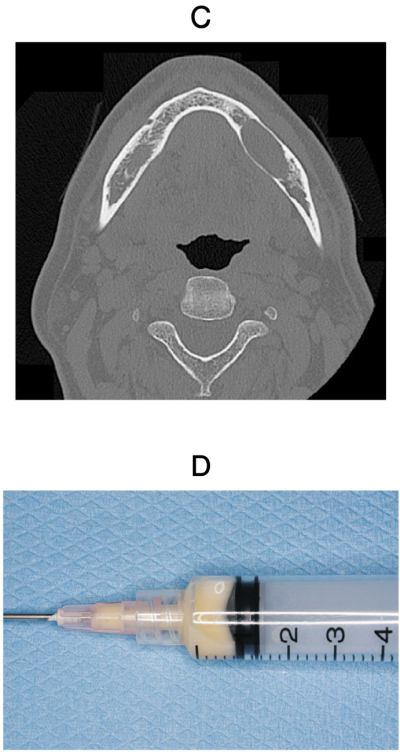

55歳の男性。下顎左側臼歯部の腫脹を主訴として来院した。5年前に気付いたがそのままにしていたという。診察の結果、生検と開窓を行うこととした。初診時の口腔内写真、エックス線写真、CT、生検前の穿刺液及び生検時のH-E染色病理組織像を別に示す。

診断はどれか。1つ選べ。

e. 角化囊胞性歯原性腫瘍